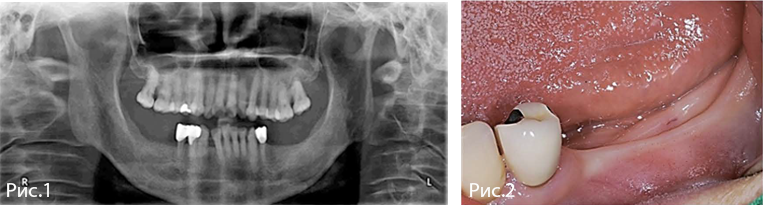

Рис. 1—2. Исходная рентгенологическая и клиническая картина.